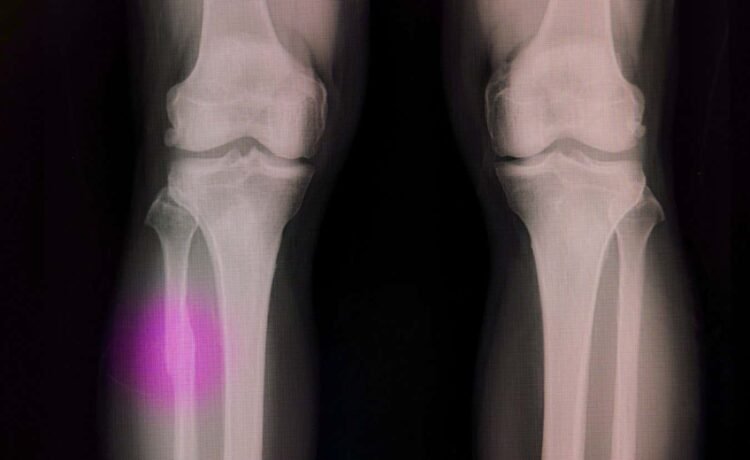

Broken bones often need a material to fill the void

Bones can repair themselves after small injuries, but if there is a void – because of serious trauma or tumour removal, for example – then that space needs to be filled with either a graft or an artificial plug made of a material that encourages bone cells to spread.